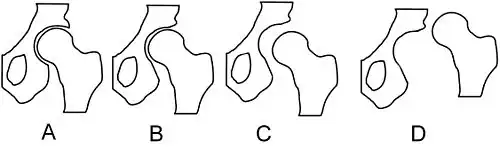

Дисплазия тазобедренного сустава может проявляться не только в виде нарушения вертлужной впадины (ацетабулярная дисплазия), но и в виде неправильного развития проксимального отдела бедренной кости. Форма данного отдела чаще всего описывается шеечно-диафизарным углом (ШДУ), который образован срединной линией диафиза и линией, проведённой через центры головки и шейки бедренной кости. Эти измерения проводят на фронтальной рентгенограмме.

В зависимости от величины этого угла и от того, насколько он соответствует возрастной норме, различают нормальную форму проксимального отдела бедренной кости, дисплазию с увеличением этого угла – coxa valga, дисплазию с уменьшением этого угла — coxa vara.

При этом угол, образованный этими линиями, должен приближаться к прямому. В этом заключается большой биомеханический смысл: равномерная нагрузка на головку и вертлужную впадину и нормальное развитие этих структур. Угол центрации тесно связан с формой шеечно-диафизарного отдела. В нижней части рисунка показаны некоторые формы дисплазии тазобедренного сустава, связанные с нарушением шеечно-диафизарного угла и угла наклона вертлужной впадины. Рисунок А – норма. Линия наклона вертлужной впадины и срединная линия головки и шейки составляют прямой угол, ШДУ и угол наклона вертлужной впадины не изменены. Рисунок Б – варусная деформация проксимального отдела бедра с нарушением центрации. Рисунок В показывает форму дисплазии с увеличением ШДУ при нормальном угле наклона вертлужной впадины. Рисунок Д – дисплазия, при которой сочетается избыточный ШДУ и избыточный угол наклона вертлужной впадины[12].